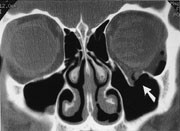

Mukocele er vanlig årsak til smertefri proptosis, ofte utgående fra frontal eller etmoidal sinus, og kan erodere beinet og gi falskt inntrykk av destruksjon (fig 11 a,b). Innholdet i mukocele er ofte homogent. Etter kontrast sees en tynn perifer brem; den innvendige mucosa tar opp kontrast (13).